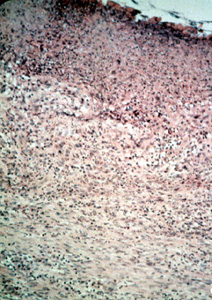

Esta microfotografía de baja resolución  ilustra bien el aspecto lobulado de la lesión. Hay una invaginación profunda en la porción central en que la pestaña de la dentadura postiza fue localizada.

Este microfotografía se observa el área ulcerada en la base de la invaginación y muestra exudado inflamatorio, tejido fibroso reactivo  y tejido de granulación.

Periférico a la ulceración el tejido del tipo predominante que comprende la mayoría de la lesión, es el tejido conjuntivo fibroso bastante denso con un número moderado de los vasos sanguíneos. Note la inflamación crónica perivascular  tan común en las lesiones reactivas. Los fibroblastos son uniformes a lo largo  hay  considerable colágeno denso. Con esta microfotografía usted puede determinar que la única forma de eliminar la lesión es con la biopsia por escisión.